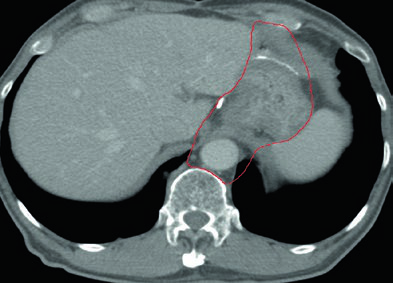

Deve-se considerar estudo de perfusão renal quantitativa bilateral antes da radioterapia, pois a função renal pode limitar o planejamento. A TC pós-operatória com contraste oral e intravenoso é obrigatória, com identificação precisa do esôfago e remanescente gástrico, da anastomose (gastrojejunal ou esofagojejunal), do coto duodenal, da porta hepática, do hilo esplênico, do pâncreas, e da artéria celíaca e artéria mesentérica superior.

Imobilização com saco a vácuo tipo VacLok é recomendada para tratamento com IMRT. Contraste intravenoso é preferido para demonstrar os vasos sanguíneos e guiar o delineamento do CTV, particularmente para as cadeias linfonodais.